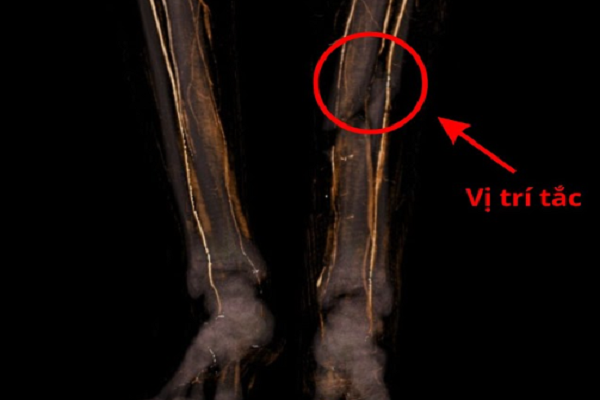

Ngay lập tức, bệnh nhân được kích hoạt quy trình cấp cứu khẩn cấp. Ê-kíp bác sĩ tiến hành thăm khám lâm sàng, kết hợp các xét nghiệm và chẩn đoán hình ảnh để đánh giá mức độ tổn thương.

Kết quả cho thấy bệnh nhân bị dập nát mô mềm nặng ở hai cẳng chân, kèm theo nguy cơ chèn ép khoang tiến triển nhanh. Đây là tình trạng khi áp lực trong khoang cơ tăng cao, làm cản trở lưu thông máu nuôi dưỡng mô, dẫn đến thiếu máu cục bộ và có thể gây hoại tử nếu không được giải áp kịp thời.